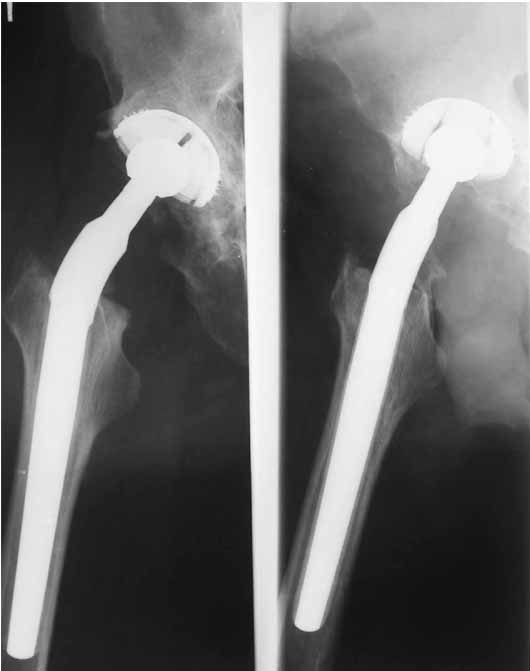

Дорогие коллеги.Мой хороший товарищ, сам травматолог-ортопед, прооперирован 1,5 мес назад. Естественно, начались проблемы. Хотелось бы узнать ваше мнениеи, главное,что делать дальше... Итак:Мужчина 50 лет.Д-з: Посттравматический деф.артроз правого тазобедренного сустава с выраженным болевым синдромом, стойкой комбинированной контрактурой иукорочением 3 см. Анамнез: 10 лет назад - сочетанная травма головы, груди, конечностей, таза... перелом заднего края вертлужной впадины и вывих бедра справа.Лечился консервативно. 25.05.94 - операция тотальное эндопротезирование правого тазобедренного сустава бесцементным эндопротезом (чашка Споторно 52, ножка Вагнера 225/21, головка L), дополнительная фиксация в кокситной гипсовой повязке в течение 3 нед. Спустя месяц после операции при поворачивании на бок в кровати произошел вывих головки эндопротеза. Под наркозом вывих вправили. Вот 10 дней лежит в постели. Что необходимо делать? Рентгенограммы до операции и после. Рентгенограммы в положении вивиха у меня отсутствуют. Ну наверное они и не столь важны, ведь вывих-то вправили. Учреждение и фамилию пациента, нашего коллеги, называть не буду. Он попросил меня собрать мнения - как ему жить дальше. Заранее благодарен. С уважением Александр Артемьев

Если же вывих произошел по причине неправильной ориентации ножки (чего по снимкам нельзя исключить), то конечно же он будет повторяться и

постельный режим тут ничем не поможет. Необходима ревизия с заменой неправильно имплантированного компонента и тщательным восстановлением капсулы и мышц в зоне сустава...

Первые впечатления:

1. Вертикальное положение чашки;

2. Нарушение угла антеверсии ножки (судя по изображению малого вертела

на послеопреационной рентгенограмме).

3. Комбинация этих двух причин.

4. Видимо, тенденция к вывиху была уже на столе - вот Вам и кокситная повязка с надеждой на фиксацию протеза рубцом.

Сан Саныч,

Консультировать вывихи по рентгенограммам, не зная хода операции, дело не очень благодарное. Я думаю, что с датой операции Вы ошиблись и это был 2004 год? Тем не менее. Настораживают два фактора. Первое - не видно большого вертела. Если с мышцами обошлись грубо и их отсекли, то это очень грустно и нужна "связанная" пара, т.н. "constrain cup". Смущает хорошо прослеживаемый малый вертел и небольшая ретроверсия чашки. Возможно это (избыточная ретроверсия ножки и чашки) могло послужить причиной вывиха. Обычно гипсовая повязка после операции не накладывается, значит, были глубокие сомнения у оперировавшего хирурга. В этом случае - ревизия с перестановкой как минимум - ножки, а как максимум - обоих компонентов.

1. AP X ray of the Pelvis is a must. It will likely show that right hip/ femur is longer than left. Even based on Rt Hip AP X Ray it is my impression.

2. 2. Acetabular component is not vertical but rather anteverted, and also small ( small size was likely used because of the deficient posterior wall of the acetabulum).

3. Femoral component is malaligned relatively to the acetabular and combination of this factors (head is also small for this patient) is the reason for dislocation.( was likely anterior)